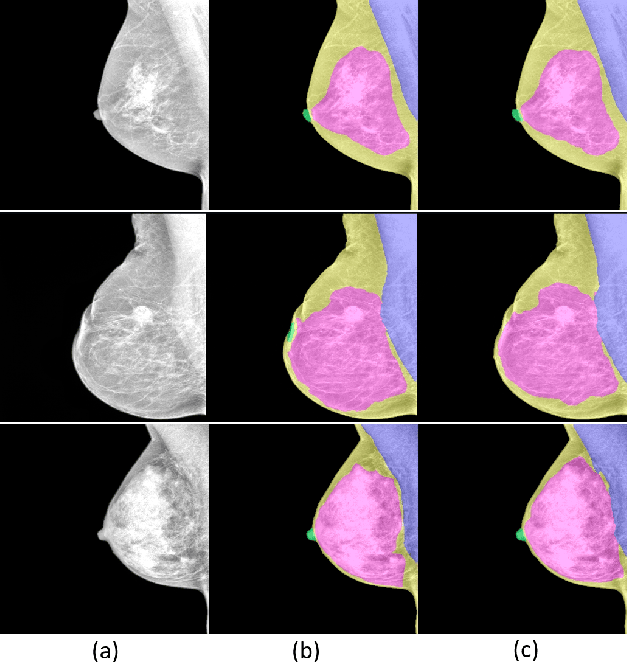

Abstract:Mammography stands as the main screening method for detecting breast cancer early, enhancing treatment success rates. The segmentation of landmark structures in mammography images can aid the medical assessment in the evaluation of cancer risk and the image acquisition adequacy. We introduce a series of data-centric strategies aimed at enriching the training data for deep learning-based segmentation of landmark structures. Our approach involves augmenting the training samples through annotation-guided image intensity manipulation and style transfer to achieve better generalization than standard training procedures. These augmentations are applied in a balanced manner to ensure the model learns to process a diverse range of images generated by different vendor equipments while retaining its efficacy on the original data. We present extensive numerical and visual results that demonstrate the superior generalization capabilities of our methods when compared to the standard training. For this evaluation, we consider a large dataset that includes mammography images generated by different vendor equipments. Further, we present complementary results that show both the strengths and limitations of our methods across various scenarios. The accuracy and robustness demonstrated in the experiments suggest that our method is well-suited for integration into clinical practice.

Abstract:Mammography images are widely used to detect non-palpable breast lesions or nodules, preventing cancer and providing the opportunity to plan interventions when necessary. The identification of some structures of interest is essential to make a diagnosis and evaluate image adequacy. Thus, computer-aided detection systems can be helpful in assisting medical interpretation by automatically segmenting these landmark structures. In this paper, we propose a deep learning-based framework for the segmentation of the nipple, the pectoral muscle, the fibroglandular tissue, and the fatty tissue on standard-view mammography images. We introduce a large private segmentation dataset and extensive experiments considering different deep-learning model architectures. Our experiments demonstrate accurate segmentation performance on variate and challenging cases, showing that this framework can be integrated into clinical practice.